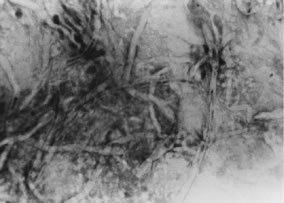

In the early stages of infection, filamentous fungi produce signs that are readily distinguishable from yeast or bacterial keratitis. The most distinctive sign is the presence of delicate, fine, feathery, opalescent, gray-white or yellow-white material in the anterior stroma, surrounded by scant cellular infiltrate or edema (Fig. 1). The epithelium may be intact. The overlying epithelium may be granular and the surface elevated and irregular in contour. Linear infiltrates typically extend into the adjacent stroma. Multiple discrete opacities may develop outside the perimeter of the principal focus of inflammation, either separated by clear stroma or linked by fine linear collections of inflammatory cells and material (Figs. 2 and 3). In the absence of inflammation in the adjacent stroma, branching hyphal fragments may be visualized by biomicroscopy (Figs. 4 and 5). Confocal microscopy may also detect hyphal elements within the stroma.28,29 Peripheral infection resembles noninfectious marginal infiltrative and ulcerative keratitis (Fig. 6). Multifocal keratitis may develop after contact lens wear or injury by multiple projectiles (Fig. 7). In the early stages, iritis is present and the intraocular pressure remains normal. Inappropriate, empirical therapy of fungal keratitis with topical fluoroquinolone or aminoglycoside antibiotics may suppress or eliminate the superficial elements but allow extension of the organisms into the stroma because these agents may possess selective antifungal activity.4,30,31

There is no distinguishing clinical sign by which to recognize the genus or species of the infectious filamentous fungus. F. solani is the most virulent organism and typically produces rapidly progressive infection characterized by epithelial and stromal ulceration, dense stromal necrosis, abundant cellular infiltrate, and edema in the adjacent stroma and hypopyon (Figs. 8 and 9). Delicate feathery components are transient. Individual hyphal fragments are rarely visualized. Infection by certain species of Aspergillus and Scedosporium (Figs. 10 and 11) resembles F. solani keratitis and progresses rapidly. Infection by less virulent organisms, such as Curvularia and Alternaria species, produces small, focal (less than 3-mm diameter) areas of nonnecrotizing stromal inflammation with delicate feathery borders (see Fig. 1 and Fig. 12). Macroscopic pigmentation may develop in keratitis caused by Alternaria, Curvularia, and other dematiaceous fungi (Fig. 13).4,11,14 The central component may progress to dense, opaque, gray-white suppuration in the deep stroma without enlargement in total area and may be accompanied by mild inflammation in the adjacent stroma. Iritis is minimal to moderate. Infection caused by other, relatively less virulent organisms resembles herpes simplex or noninfectious keratitis (Fig. 14).

Keratitis caused by Nocardia, nontuberculous Mycobacterium, and other low-virulence bacteria resembles filamentous fungal keratitis by the presence of intact epithelium, multiple stromal infiltrates, and minimal inflammation in the adjacent stroma.